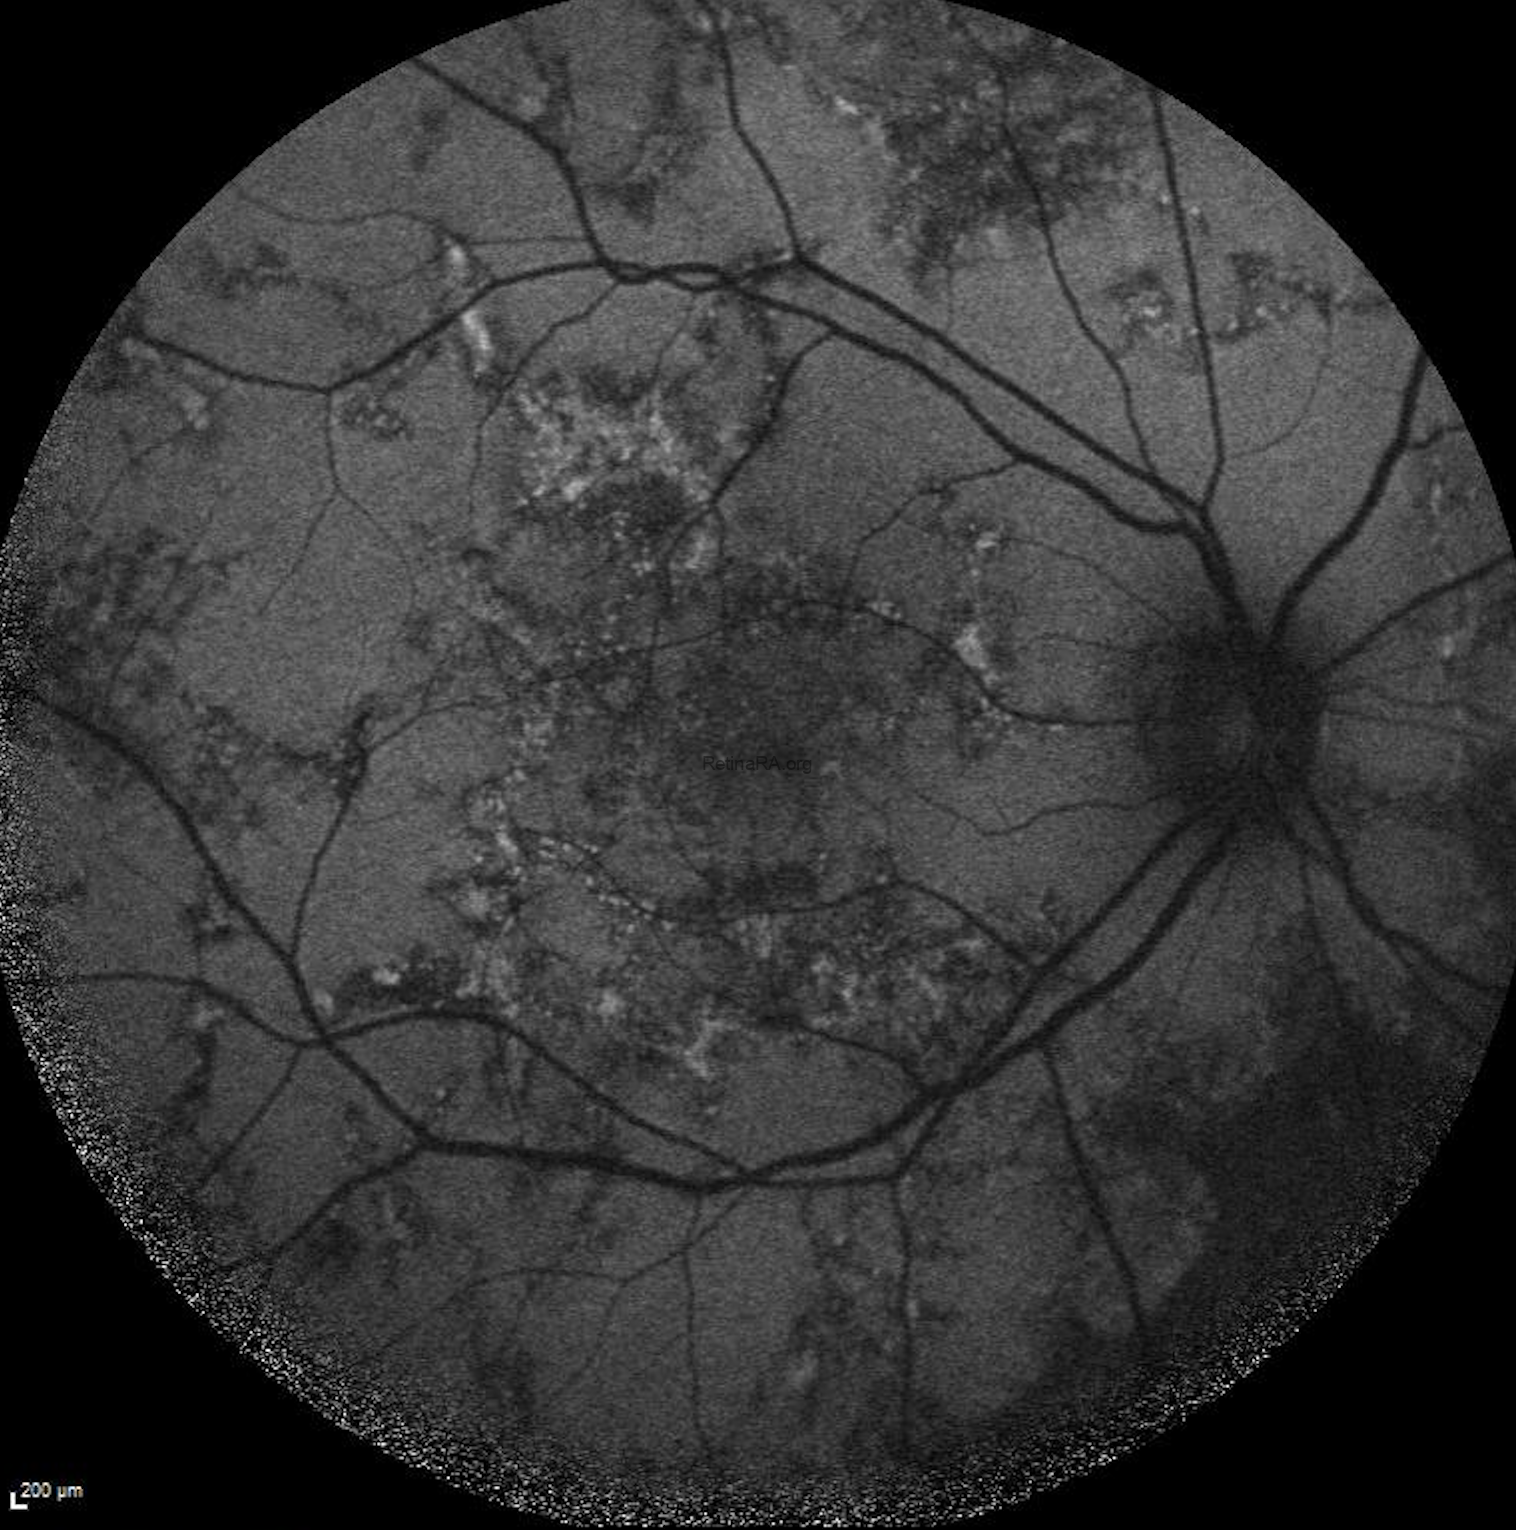

It is noteworthy that active lesion margins are hyperautofluorescent on FAF imaging.

FFA shows a marked hyperfluorescence at the lesion margins.

The quantiferon-TB test was positive and the patient was diagnosed with Tubercular serpiginous‑like choroiditis. Anti tubercular treatment (ATT) was started and then oral steroid was added. Healed lesions showed hypoautofluorescence on FAF.